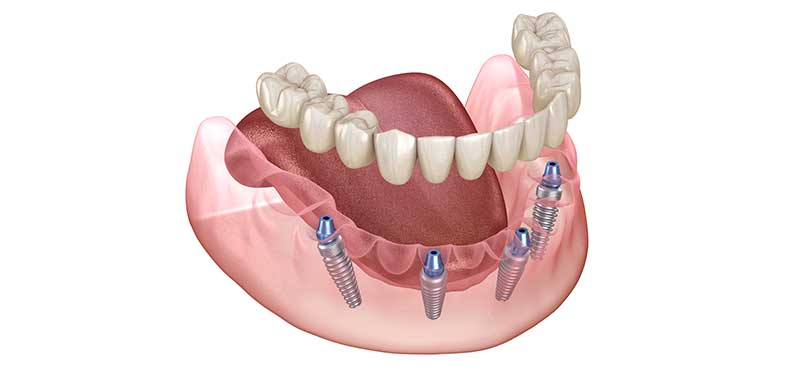

オールオンフォー(All-on-4)オールオンシックス(All-on-6)では、骨のある部分へ最少4本のインプラントオペで全ての人工の歯を支えることができます。

オペから6か月後にCTを撮影してインプラントの状態を確認し問題がなければ歯茎の調整をしてインプラントと義歯をネジでつなげる作業をします。

これをすることにより取り外しのできない入れ歯に変化します。お食事もとりやすくなりしゃべりやすくなります。

完成形をイメージしかみ合わせや歯の並びなどをよく見ていただきます。